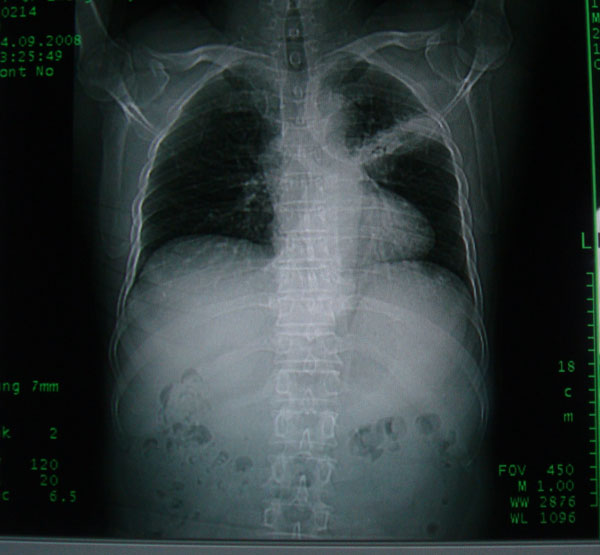

患者男性58岁因二周前起咳嗽,今天胸片示左上肺占位性病变行ct检查,无发热,无咯血痰.

左上肺感染性病变,结核伴空洞形成可能,左上肺膨胀不全

左肺上叶病灶,实变但见含气支气管、空洞但未见壁内结节及积液;

考虑:①感染性病变(包括特殊感染型肺tb)

②肿瘤性病变(考虑患者年龄比较大的关系/所以不排除)

初学者。。。左肺空洞性病变,并可见阻塞性肺不张改变,鉴于患者为老年男性,且临床症状仅有咳嗽,全身中毒症状不明显,所以我首先考虑为左肺癌性空洞并左侧肺门淋巴结转移伴左肺阻塞性肺不张。结核性空洞放于第二位考虑,可以进行相关实验室检查。希望能有病理结果,谢谢!!!!!

左肺上叶实变影,内见支气管充气征及空洞影,病人年龄较大,无发热及结核中毒症状,心影左移,未见纵隔淋巴结肿大;不知实验室检查结果如何?有否嗜酸细胞增多,有没有进行治疗?就目前资料首先考虑1.感染性病变,2.慢性嗜酸性肺炎?可结合实验室检查并短期治疗复查,肺癌不能排除。